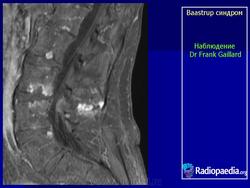

"Бааструпа (Baastrup) болезнь, osteochondrosis interspinalis, arthrosis interspinal, kissing spine, описана в 1932 г. Характеризуется наличием хронических воспалительных изменений в остистых отростках позвонков. Вследствие этого возникают длительно удерживающиеся боли в поясничном отделе позвоночника, особенно при чрезмерном изгибе его кзади или чрезмерной нагрузке (поднимание тяжестей), с местной болезненностью в области остистых отростков. На рентгенограмме видны расширенные остистые отростки со склеротическими краями, иногда на верхнем или нижнем крае отростка остеофиты, которые могут даже соприкасаться между собой. Этиология-врожденное, неправильное развитие остистых отростков поясничных позвонков; заболевание наблюдается в определенном возрасте (30-40 лет) и у людей определенных профессий (грузчики).

Следует учитывать и относительную частоту неоартроза между остистыми отростками - межостистый диартроз (Meyer Н., 1924), «целующиеся отростки» (BrailsfordJ., 1929; Baastrup С, 1933). Синдром Бааструпа может сопровождать межпозвонковый остеохондроз (Forrai J., Tannai J., 1962). Е.С.Заславский и соавт. (1973) среди больных поясничным остеохондрозом определяли клинические и рентгенологические признаки синдрома Бааструпа в 5,5%. Боли при данном синдроме по характеру тупые, ноющие, сверлящие. Они усиливаются после длительного сидения, переноски тяжестей, при разгибании туловища. Выявляются болезненность и ограничение подвижности позвоночника (особенно в позе разгибания) на уровне пострадавших двигательных сегментов, болезненность при пальпации соответствующих межостистых промежутков. При вызывании феномена вибрационной отдачи в области поясничных межостистых связок боли, как правило, не только усиливаются, но и иррадиируют в пределах скле-ротома: в крестец, ягодицу, бедро. Инфильтрация же 1-2 мл 1% раствора новокаина межостистого промежутка быстро снимает эти феномены. Синдром связывают с поясничным гиперлордозом, структуральным сколиозом, переломом и вывихом позвонков, деформирующим спондилезом с аномальным увеличением остистых отростков. С.А.Рейн-берг (1964) относил изменения остистых отростков при данном синдроме к явлениям патологической перестройки костной ткани, обусловленной нагрузками чрезмерной силы на задние отделы позвоночного столба. Согласно N.Fellmann (1964), формирование сустава между остистыми отростками проходит следующие стадии: межостистый остеосклероз, фасетирование и склероз, тяжелое артрози-рование, анкилоз.

Рисунок 1